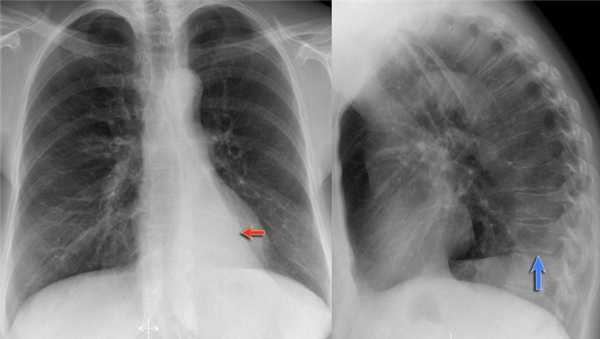

Обратите внимание на правую границу сердца. Правая междолевая артерия не видна потому, как она не окружена воздушной легочной тканью, а закрыта спавшейся нижней долей правого легкого.

Ниже представлены последующие рентгенограммы органов грудной полости того же пациента, на которых ателектаз разрешен.

Обратите внимание на правую междолевую артерию (красная стрелка) и границы правых отделов сердца (синяя стрелка).